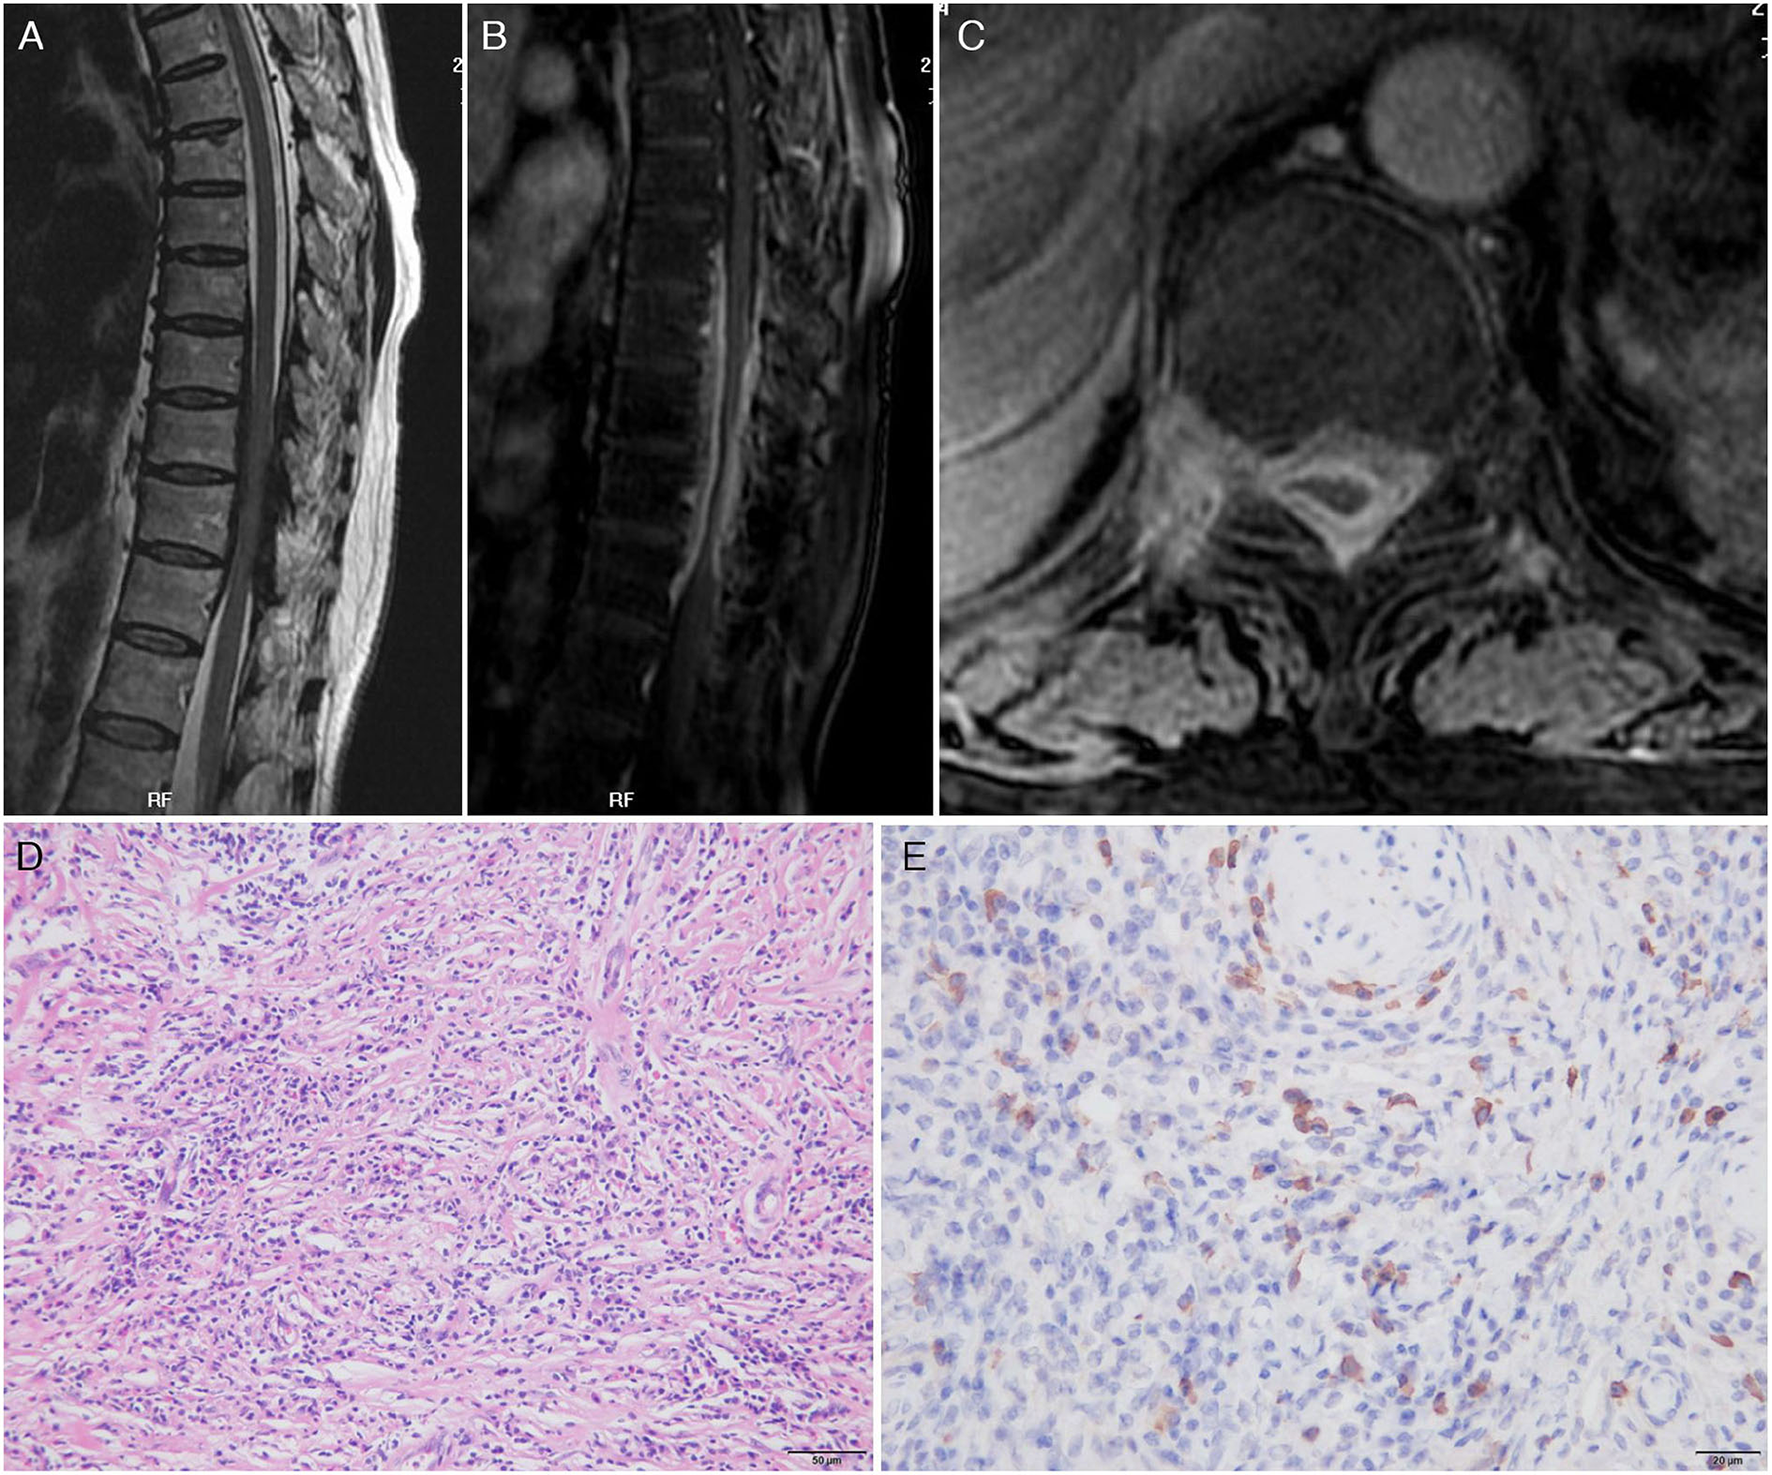

The third patient was a 61-year-old woman admitted for weakness and stiffness in both lower limbs for about 1 year, accompanied by thoracic back pain and constipation for 8 months. The neurological examination on admission revealed paresis in the bilateral lower limbs (3 to 4/5), decreased pain and thermal sensation in the trunk and lower limbs below the T10 level, brisk bilateral knee and Achilles tendon reflexes, and bilateral extensor plantar response. The routine blood tests and inflammatory markers levels were normal. Infections assays were negative. Rheumatologic assays were negative, except for seropositivity for perinuclear ANCA (titer, 1:32), MPO-ANCA (titer, 1:100), and elevated IgG4 (441 mg/dl). Chest and paranasal sinus CT found no abnormalities. A spinal cord MRI revealed a ribbon-like thickening of the dura mater between vertebral levels T7 and T11 (which was moderately enhanced by gadolinium administration) and a compressed and flattened focal spinal cord (Figures 3A–C). Although the patient underwent emergent T7–T11 right pediculectomy and partial corpectomy for decompression and resection of the dural lesion, her neurological deficits did not improve. The CSF analysis during the operation was negative for bacteria, tuberculosis, viruses, and fungi. A broad panel of immunohistochemical markers was assayed, such as S-100, EMA, CK-P, GFAP, Vim, CD20, CD68, CD38, CD138, CD34, and Ki67. A histopathology analysis showed lymphocyte infiltration, high IgG4+ cell infiltration, and a storiform pattern of fibrosis without granulomatous changes (Figures 3D,E).

Figure 3

Magnetic resonance imaging scan of the thoracic spine on admission and pathology findings. Sagittal T2-weighted image (A) showed a low-signal intensity lesion in the anterior and posterior epidural spaces and high enhancement after gadolinium enhancement (B) at the thoracic canal between T7 and T11 vertebral body levels. Axial images showed that the lesion was located in the epidural space and extended to the neural foramen to the right. A fat-suppressed T1-weighted image with gadolinium enhancement demonstrated high enhancement of the mass (C). Pathology findings: Hematoxylin and eosin stain of the epidural mass showed intense lymphoplasmacytic inflammatory cell infiltrate with fibrosis. Plasma cells and lymphocytes were also detected within the wall of a vessel as well as in the perivascular area (D). IgG4 immunohistochemistry showed prominent IgG4+ cells within the inflammatory infiltration. Nearly more than half of the plasma cells exhibited IgG4 reactivity (E).